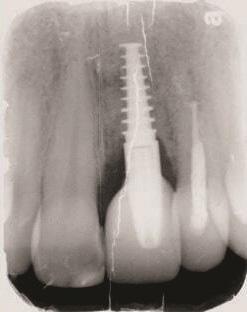

Пациент 1: Пациентка 30 лет с неосложненным медицинским анамнезом обратилась с имплантатом № 2.1, у которого диагностирован ретроградный периимплантит. Зуб № 2.1 был заменен имплантатом 8 лет назад из-за травмы в анамнезе и неудачного лечения корневых каналов. Имплантат демонстрировал периапикальную рентгенопрозрачность со свищевым ходом, ведущим к верхушке имплантата № 2.1 (Фото 1 и Фото 2). У пациентки была высокая линия улыбки с более длинными клиническими коронками зубов №№ 2.1 и 2.2 по сравнению с №№ 1.2 и 1.1 (Фото 1 и Фото 2).

Фото 1 и Фото 2. Случай 1: Первоначальная клиническая картина с гуттаперчевым штифтом, установленным в апикальный свищ зуба № 2.1 (Фото. 1); рентгеновский снимок, показывающий гуттаперчевый штифт, ведущий к периапикальному поражению (Фото. 2).